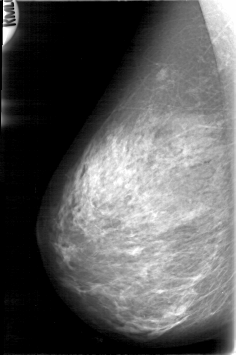

D_4082_1.LEFT_MLO

RIGHT_CC LINES 5266 PIXELS_PER_LINE 3241 BITS_PER_PIXEL 12 RESOLUTION 43.5 NON_OVERLAY

RIGHT_MLO LINES 5311 PIXELS_PER_LINE 3526 BITS_PER_PIXEL 12 RESOLUTION 43.5 NON_OVERLAY